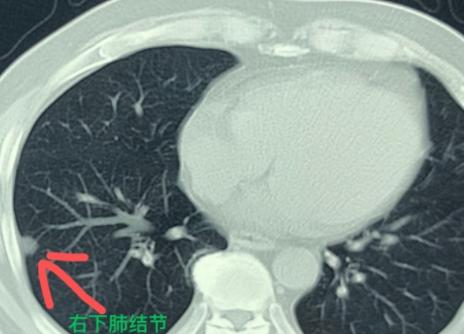

肺多发结节的手术,在我看来,不单是技术活,更像是一门“艺术”!前段时间,有位60